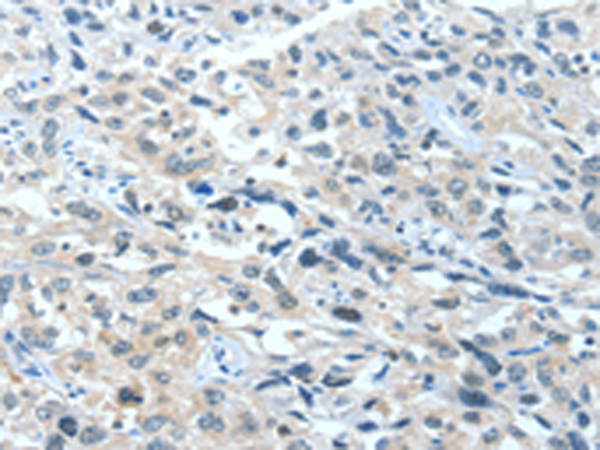

分类: 科研抗体货号: P06988别名: BCL2L4应用: WB,IHC反应种属: Human, Mouse, Rat